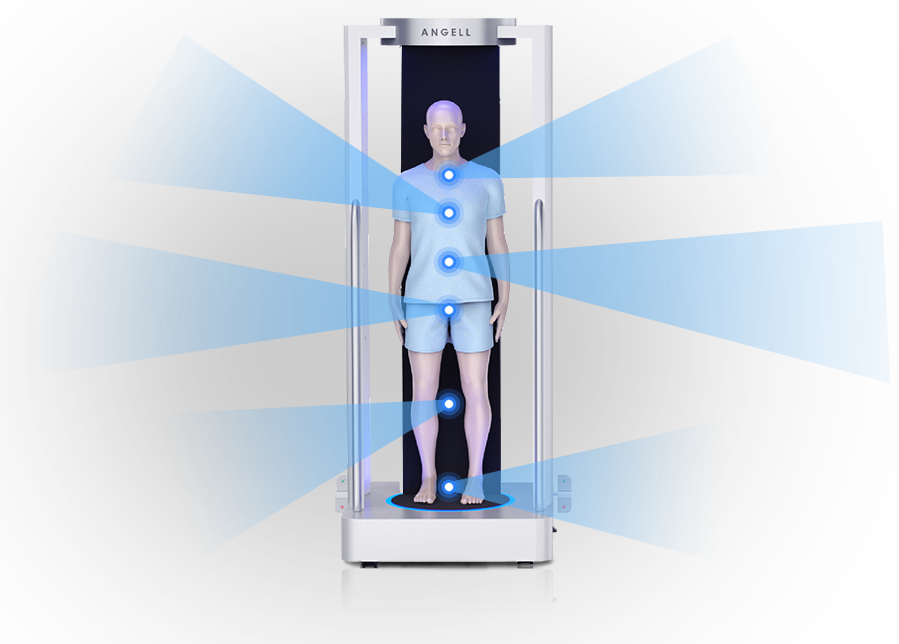

獨特的負重位

三維影像

三維影像

全身覆蓋

可移動式站臺設(shè)計

可移動站臺

2D+3D一站式快速檢查